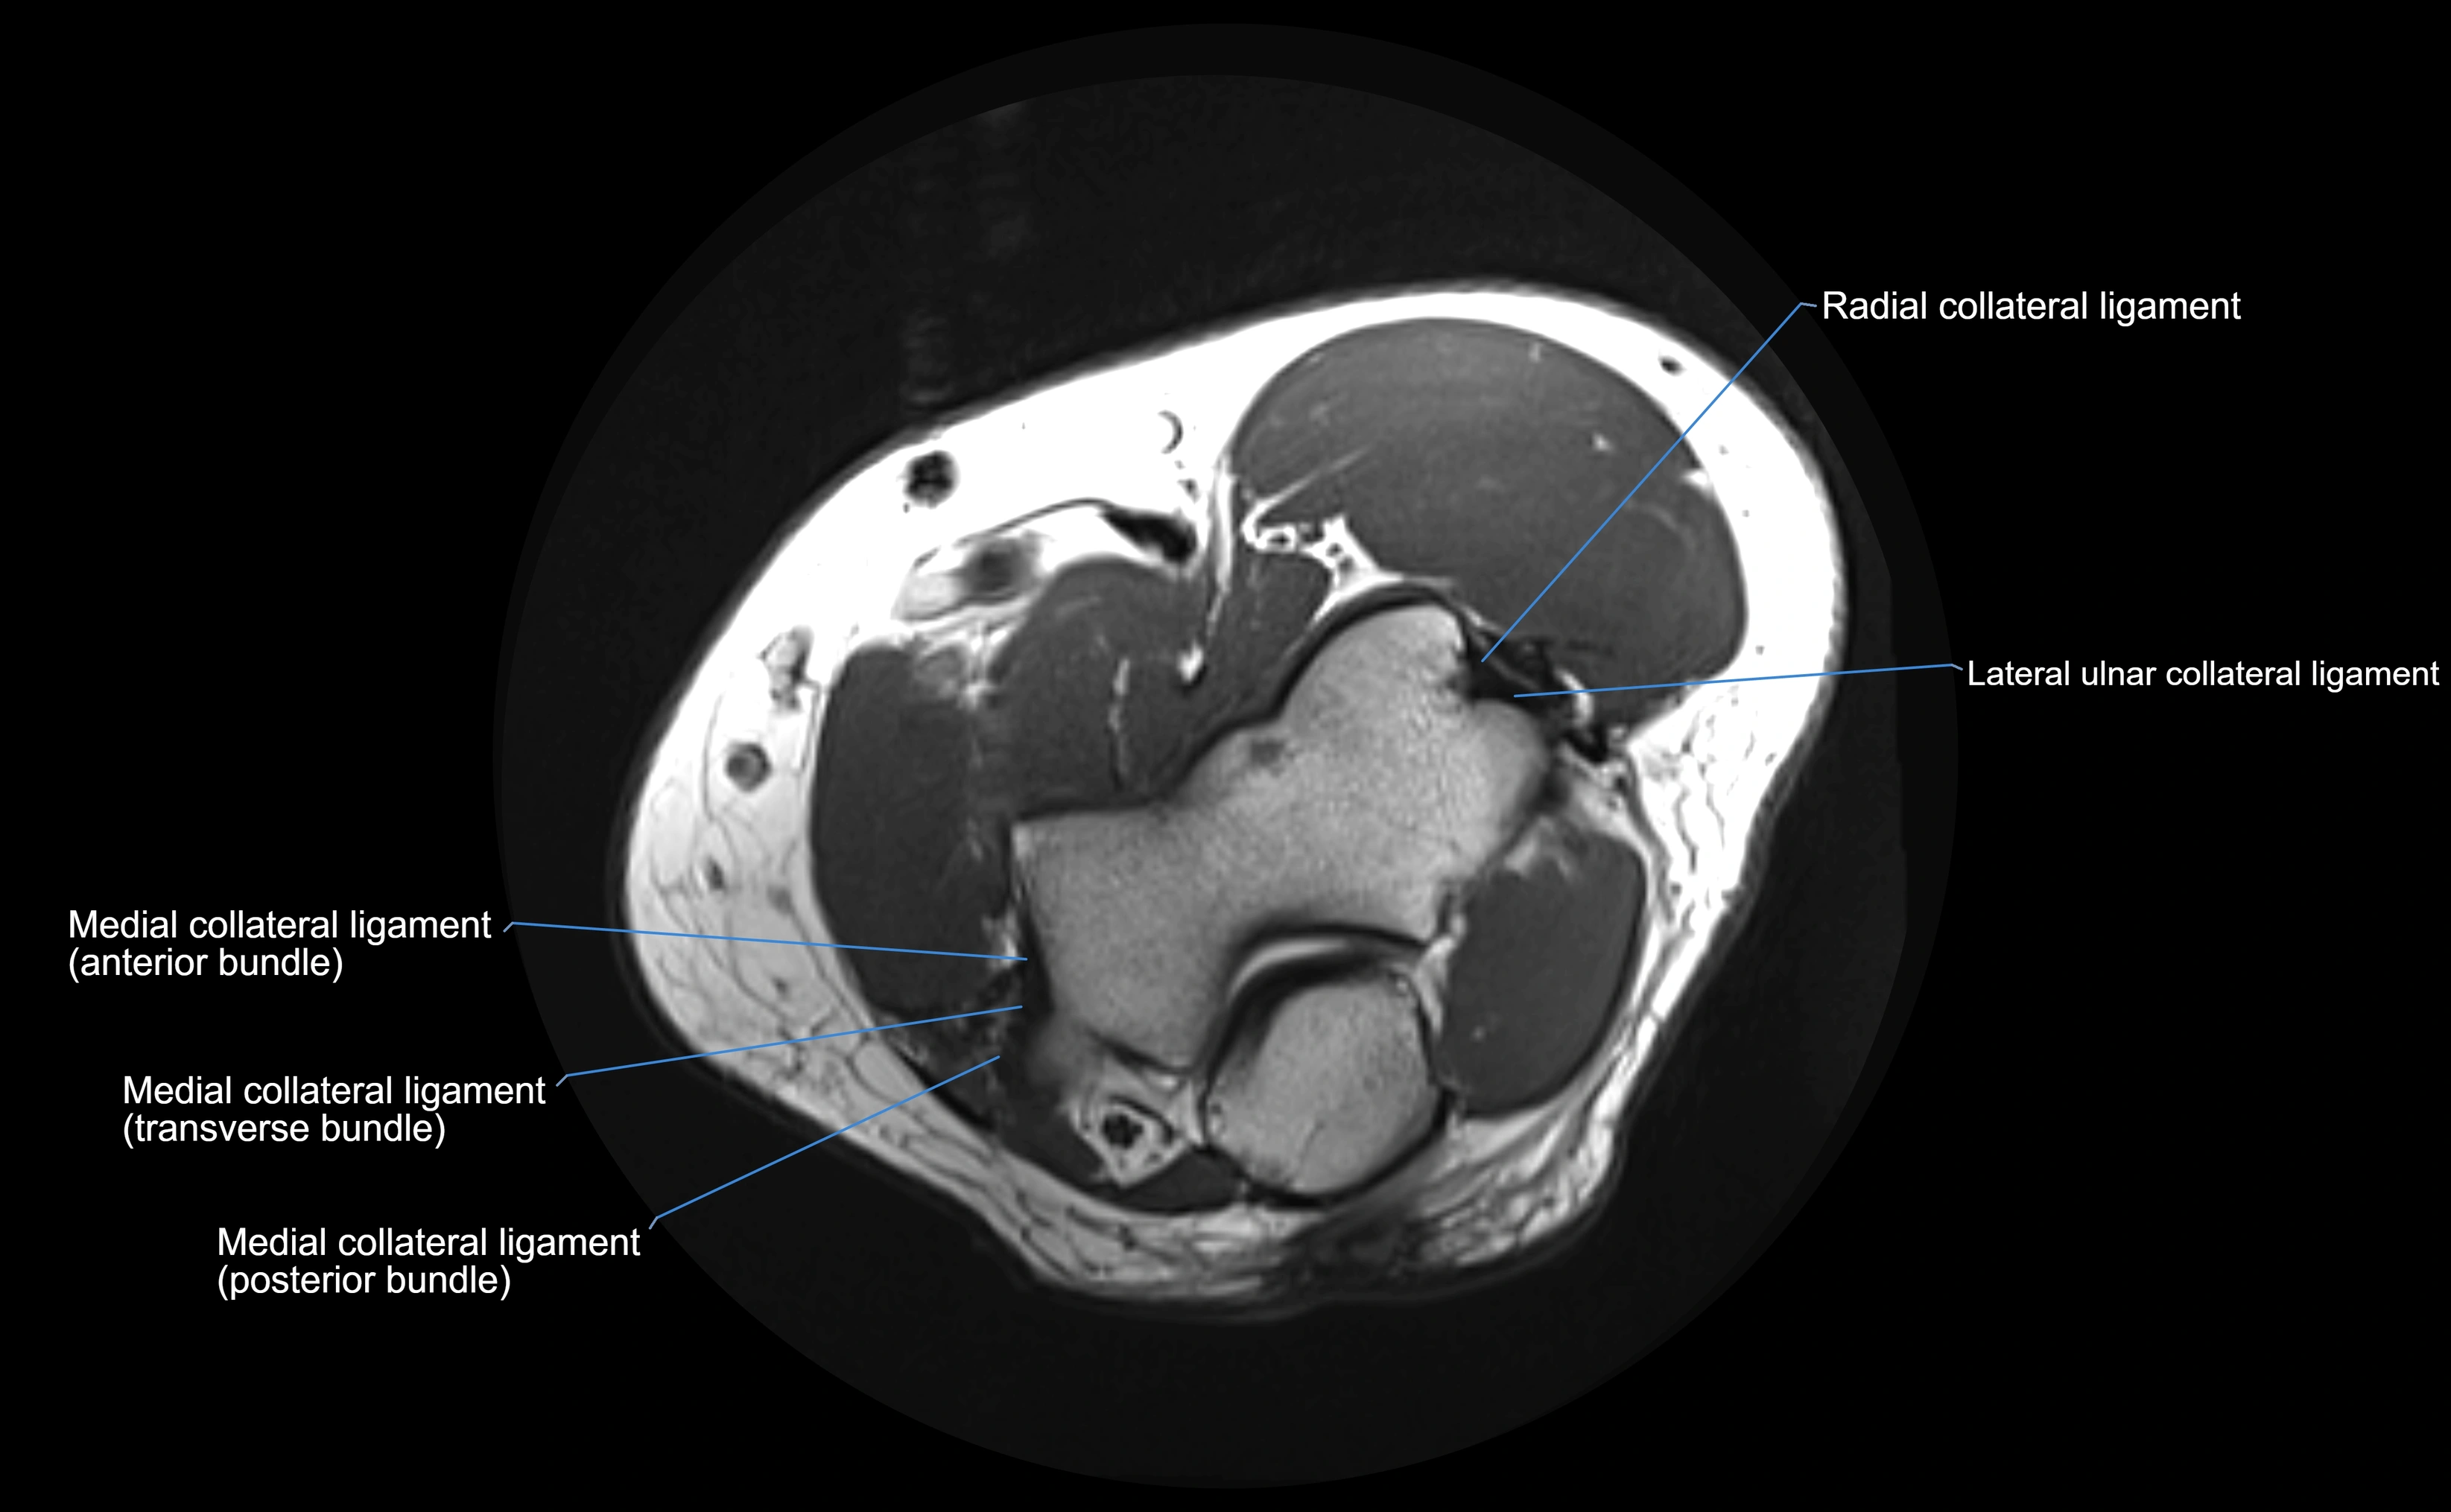

MRI Appearance

T1-weighted images:

• Ligament: low signal intensity (dark), appearing as a continuous band around the radial head.

• Adjacent fat and marrow: bright, creating contrast with the ligament.

• Thickening or disruption indicates injury or fibrosis.

• Joint capsule and synovium seen as thin low-signal lines contiguous with ligament margins.

T2-weighted images:

• Ligament: low signal (dark) with clear delineation from joint fluid.

• Fluid or edema: bright hyperintense, separating or surrounding the ligament in partial tears.

• Complete tear: discontinuity or non-visualization of ligament fibers, often with joint effusion.

STIR:

• Normal ligament: dark band encircling radial head.

• Pathology: bright hyperintense periligamentous signal suggesting edema, sprain, or partial tear.

Proton Density Fat-Saturated (PD FS):

• Normal: dark, well-defined band outlining the radial head.

• Partial tear: irregular or bright hyperintense signal within or adjacent to ligament fibers.

• Joint effusion and reactive synovitis appear bright and are well visualized.